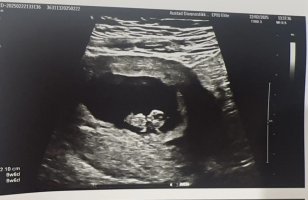

Er 6+6 i dag, men fosteret var 0,5 mm så det svarer til 6+1 ca. Så vi får håpe at det er bra! Såg to sekker, men bare ett foster. I alle fall ett godt tegn med bankende hjerte, så får vi ta det deretter!Sååå fin! Ser ut som en bitteliten baby joVar på ny UL i dag

er 8+3 men han målte til 8+5/6! Men det får jeg ikke til å stemme! Alt såg helt perfekt ut! Den bevegde seg tilogmed169 i puls

Ååå fy søren så koselig! Mini mini baby!Var på ny UL i dag